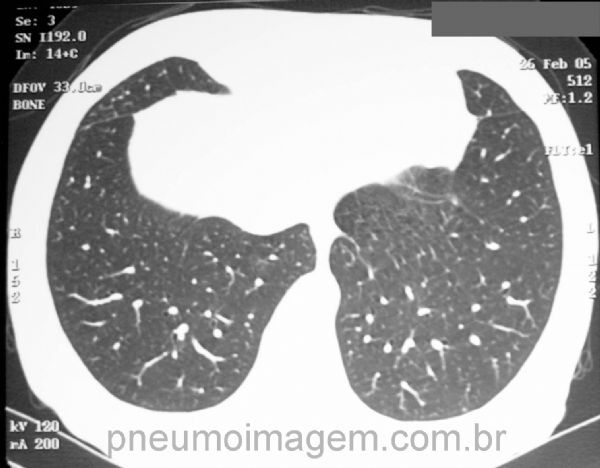

Corte tomográfico em inspiração.

CT slice of inspiration.